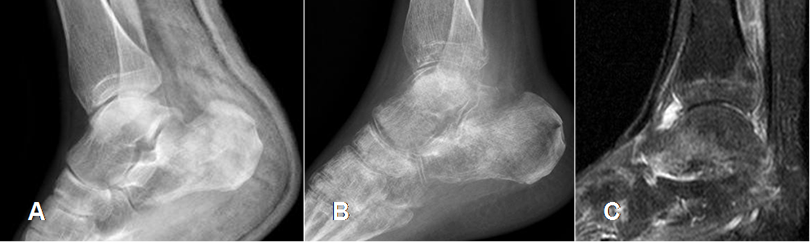

Fig 44. Artropatía neuropática. Patrón atrófico.

A: Rx lateral del tobillo, con fractura impactada del calcáneo.

B: Rx 6 meses después. Osteopenia del retropié, con resorción de calcáneo, talo y huesos del tarso.

C: RM sagital en STIR. Disminución del espacio articular, signos de sinovitis y edema óseo de la tibia y el talo.